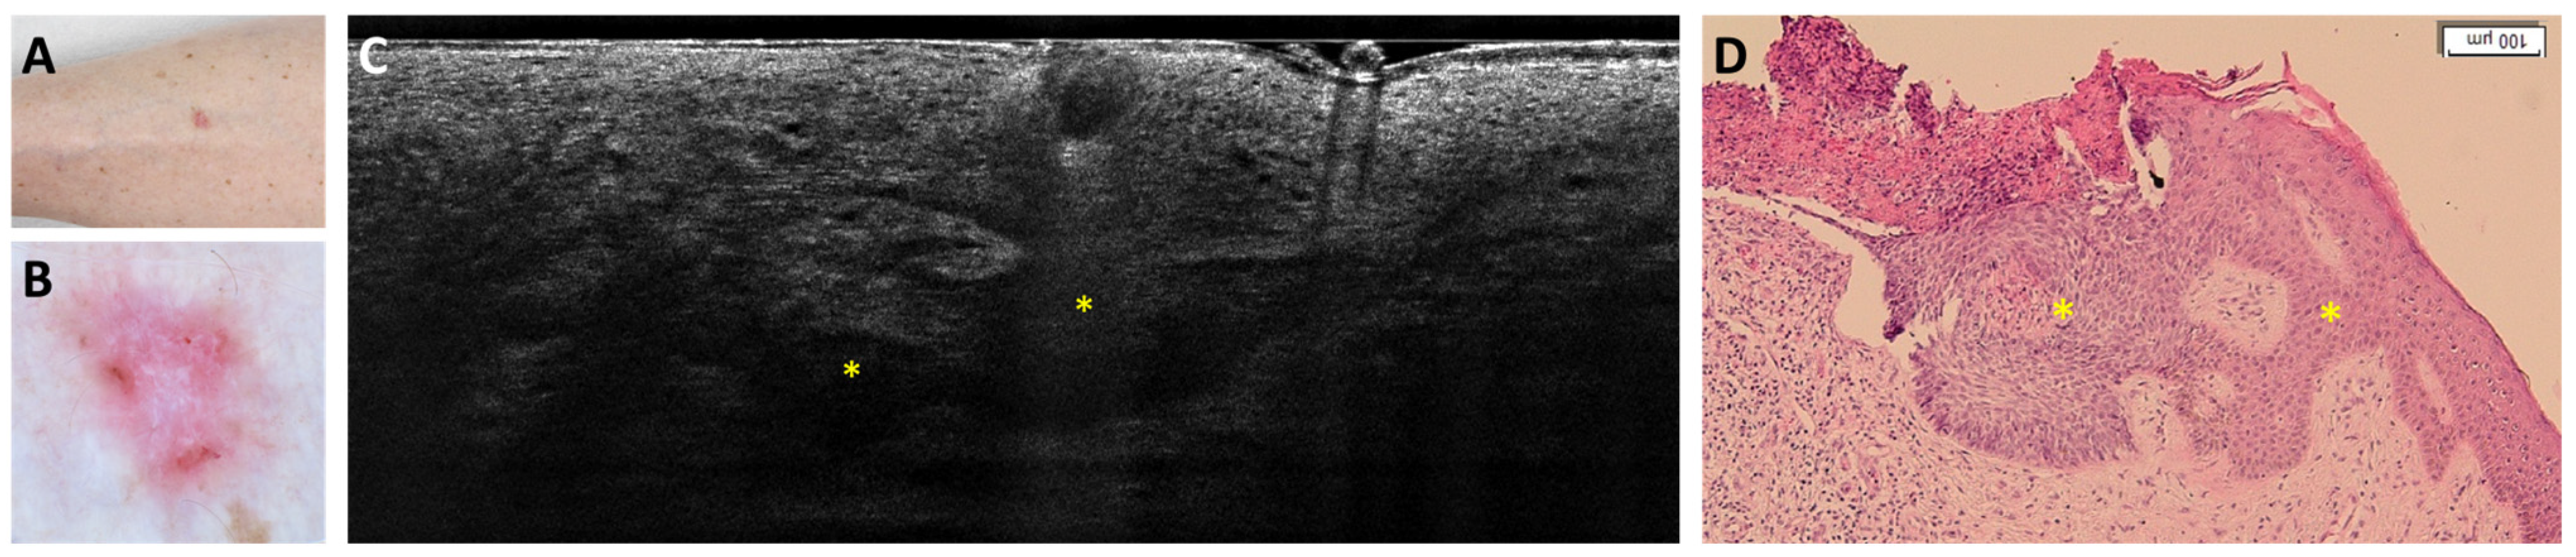

- Suppa, M.; Fontaine, M.; Dejonckheere, G.; Cinotti, E.; Yélamos, O.; Diet, G.; Tognetti, L.; Miyamoto, M.; Orte Cano, C.; Perez-Anker, J.; et al. Line-field confocal optical coherence tomography of basal cell carcinoma: A descriptive study. J. Eur. Acad. Dermatol. Venereol. 2021, 35, 1099–1110. [Google Scholar] [CrossRef]

- Ruini, C.; Schuh, S.; Gust, C.; Kendziora, B.; Frommherz, L.; French, L.E.; Hartmann, D.; Welzel, J.; Sattler, E. Line-field optical coherence tomography: In vivo diagnosis of basal cell carcinoma subtypes compared with histopathology. Clin. Exp. Dermatol. 2021, 46, 1471–1481. [Google Scholar] [CrossRef]

- Boussingault, L.; Lenoir, C.; Stefani, A.D.; Cappilli, S.; Fontaine, M.; Diet, G.; Miyamoto, M.; Cinotti, E.; Tognetti, L.; Pérez-Anker, J.; et al. Line-Field Confocal Optical Coherence Tomography of Basal Cell Carcinoma: Systematic Correlation with Histopathology. Diagnostics 2025, 15, 3059. [Google Scholar] [CrossRef] [PubMed]